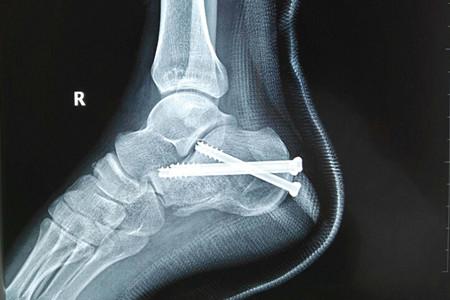

跟骨骨折以足跟部劇烈疼痛,腫脹和淤斑明顯,足跟不能著地行走,跟骨壓痛為主要表現(xiàn)。本病成年人較多發(fā)生,常由高處墜下或擠壓致傷。經常伴有脊椎骨折,骨盆骨折,頭、胸、腹傷。跟骨為松質骨,血循供應比較豐富,骨不連者少見。但如骨折線進入關節(jié)面或復位不良,后遺創(chuàng)傷性關節(jié)炎及跟骨負重時疼痛者很常見。